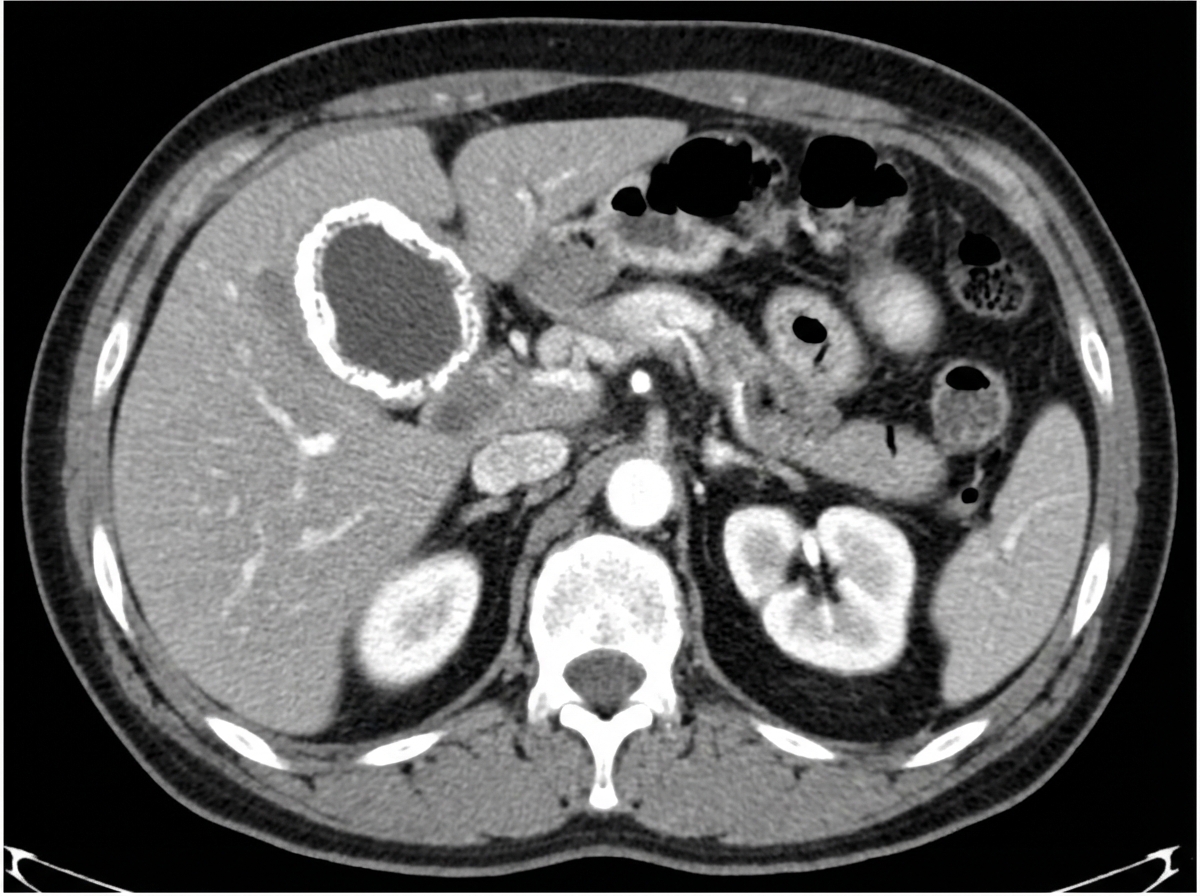

Explanation: ***Always denotes a benign etiology*** - **Porcelain gallbladder** is associated with an increased risk of **gallbladder carcinoma** (up to 25% malignancy risk). - The **calcified gallbladder wall** does not guarantee benign pathology and requires surgical evaluation. *May be seen on plain X-ray* - **Rim-like calcification** of the gallbladder wall can be visible on plain abdominal X-rays. - The **calcified wall** appears as a thin radiopaque outline around the gallbladder shadow. *More commonly diagnosed on CT* - **CECT** is more sensitive than plain X-ray for detecting **wall calcification** and associated complications. - CT provides better **soft tissue contrast** and can identify **gallbladder wall thickening** and other abnormalities. *It is an indication for cholecystectomy* - **Porcelain gallbladder** is a **relative indication** for prophylactic cholecystectomy due to malignancy risk. - **Elective laparoscopic cholecystectomy** is recommended to prevent progression to **gallbladder carcinoma**.

Explanation: **Explanation:** Right Upper Quadrant (RUQ) calcifications are frequently encountered on plain abdominal radiographs (KUB). The correct answer is **"All of the above"** because various anatomical structures located in the RUQ can undergo calcification, necessitating a systematic approach to differential diagnosis. 1. **Gallstones (Cholelithiasis):** While only about 10-15% of gallstones are radiopaque (due to calcium carbonate or bilirubinate), they typically appear as faceted or laminated calcifications in the RUQ. 2. **Renal Stones (Nephrolithiasis):** Approximately 85-90% of renal stones are radiopaque (e.g., Calcium oxalate/phosphate). These are located more posteriorly and medially compared to gallstones. 3. **Vascular Calcifications:** Calcification of the abdominal aorta or the **renal artery** can appear in the RUQ. Atherosclerotic plaques often present as linear or "track-like" opacities. **Why other options are part of the whole:** Options A, B, and C are all common causes. In clinical practice, a lateral decubitus or lateral view X-ray helps differentiate them: gallstones move anteriorly, while renal stones remain posterior (overlying the spine). **High-Yield Clinical Pearls for NEET-PG:** * **Porcelain Gallbladder:** Intramural calcification of the gallbladder wall; associated with a high risk of gallbladder carcinoma. * **Mercedes-Benz Sign:** Radiolucent gas-filled clefts within a gallstone. * **Staghorn Calculus:** Large stone filling the renal pelvis and calyces, usually composed of struvite (Magnesium Ammonium Phosphate). * **Phleboliths:** Small, rounded venous calcifications with a lucent center, often seen in the pelvis but can occur in the RUQ (hemangiomas), helping differentiate them from ureteric stones.

Explanation: **Explanation:** **Hepatocellular Carcinoma (HCC)** is the most common cause of malignant portal vein thrombosis (PVT). This occurs due to the unique biological propensity of HCC for **angioinvasion**. HCC cells frequently invade the small branches of the portal vein, eventually extending into the main portal vein trunk. On imaging (Triphasic CT/MRI), malignant thrombus is characterized by expansion of the vessel lumen and "neovascularity" (the **"Thread and Streaks" sign**), where the thrombus itself shows arterial phase enhancement, mimicking the primary tumor. **Analysis of Incorrect Options:** * **Renal Cell Carcinoma (RCC):** While RCC is notorious for venous invasion, it characteristically involves the **Renal Vein** and extends into the **Inferior Vena Cava (IVC)**, rather than the portal system. * **Carcinoma of the Prostate:** This typically spreads via the Batson venous plexus to the spine or via lymphatics; it does not have a primary association with portal vein invasion. * **Carcinoma of the Colon:** While colorectal cancer frequently metastasizes to the liver via the portal vein, it rarely causes a direct malignant thrombus within the vein itself. It is more commonly associated with *bland* (non-malignant) thrombosis due to hypercoagulability. **High-Yield Clinical Pearls for NEET-PG:** * **Imaging Gold Standard:** Contrast-enhanced CT/MRI. A malignant thrombus will show **enhancement** (matching the HCC), whereas a bland thrombus will not. * **Doppler Ultrasound:** Malignant thrombi often show **pulsatile flow** (arterialization) within the thrombus. * **Bland vs. Malignant:** Bland thrombus is common in cirrhosis/portal hypertension; malignant thrombus is a hallmark of advanced HCC and significantly worsens the prognosis (BCLC Stage C).

Explanation: **Explanation:** The investigation of choice for evaluating a renal mass is a **Contrast-Enhanced Computed Tomography (CECT)** scan. CT is the gold standard because it provides superior anatomical detail, allowing for the characterization of the mass (solid vs. cystic), assessment of enhancement patterns (crucial for diagnosing Renal Cell Carcinoma), and staging (evaluation of local extension, lymphadenopathy, and venous involvement like renal vein or IVC thrombus). **Analysis of Options:** * **CT Scan (Correct):** It is highly sensitive and specific. A mass showing enhancement of >15–20 Hounsfield Units (HU) post-contrast is highly suggestive of malignancy (RCC). * **Plain X-ray (Incorrect):** It has very low sensitivity. It may only show indirect signs like an altered renal contour or incidental calcifications, but cannot characterize a mass. * **Intravenous Pyelogram (IVP) (Incorrect):** Historically used to visualize the collecting system, IVP is poor at evaluating parenchymal masses and has been largely replaced by CT Urography. * **Renal Scintigraphy (Incorrect):** Nuclear medicine (e.g., DMSA, DTPA) is used to assess renal function and scarring, not for the primary morphological evaluation of a suspected tumor. **High-Yield Clinical Pearls for NEET-PG:** * **Bosniak Classification:** Used on CT to categorize renal cysts (I and II are benign; III and IV require surgery). * **MRI:** Reserved for patients with contrast allergies, renal failure, or when evaluating the cephalad extent of an IVC thrombus. * **USG:** Usually the *initial* investigation (screening), but CT is the *investigation of choice* for definitive evaluation. * **Triphasic CT:** The protocol includes non-contrast, corticomedullary, and nephrographic phases for optimal lesion detection.